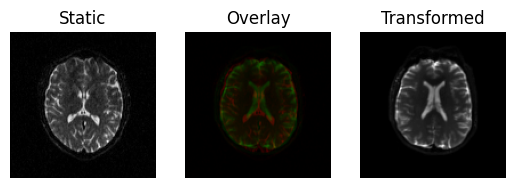

This produces a slight rotation, and the images are now better aligned

transformed = rigid.transform(moving)

<Figure size 640x480 with 3 Axes>

Registration result with a rigid transform, using Mutual Information.